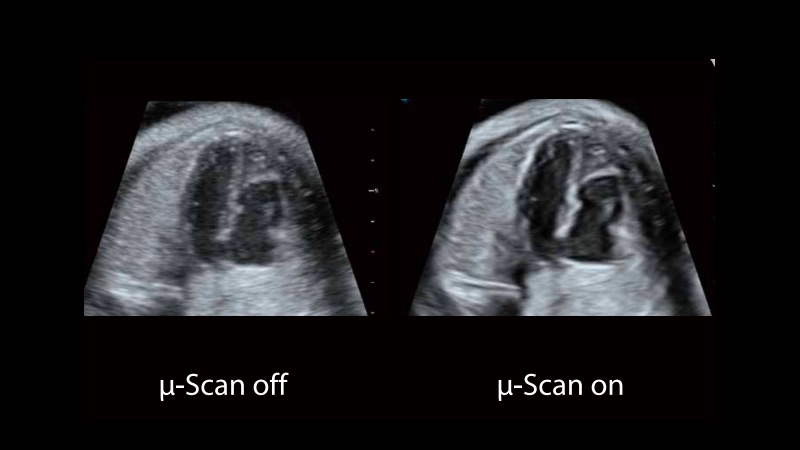

μ-Scan+新一代微米成像技術(shù)

新一代微米成像技術(shù)大大提高了器官和病變的可見性。高清對比度分辨率將抑制斑點噪聲,同時保持真實的組織結(jié)構(gòu)。